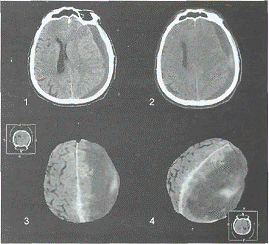

Прямая рентгенографическая диагностика ХСГ

возможна лишь в редких случаях их обызвествления. В зоне типичной

парасагиттально-конвекситальной локализации ХСГ (обычно в лобно-теменной

области) обнаруживаются петрификаты различной плотности и структуры, либо тесно

прилегающие к внутренней поверхности кости, либо очерчивающие капсулу ХСГ, либо

находящиеся в полости гематомы. Наиболее информативны краниограммы при полной

оссификации ХСГ (рис 1).